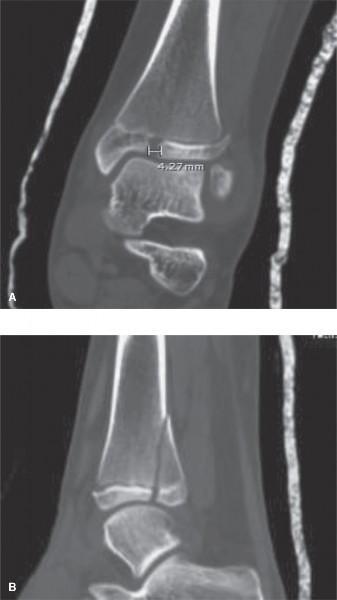

The correct answer is (D). In general, MRI is considered the “gold standard” for evaluation of soft tissue injuries, such as ligaments and tendons. dGEMRIC imaging (as its name implies) is used primarily to evaluate injury to the articular cartilage. CT scanning is generally considered the “gold standard” for evaluation of bony injury and alignment. Because your goal in evaluation post-reduction is assessment of the fracture alignment at the articular surface, a noncontrast CT scan is the best choice. Contrast enhancement in this setting would not add additional useful information. Post-reduction CT images are shown (Fig. 10–16A and B). Based on the images and measurement shown, you recommend (choose the best answer):

Illustration 8 for Pediatric Cases: Optimal Closure of the Distal Femur

Clinical Radiograph / Orthopedic Image

Figure 10–16 A–B

1. Continued immobilization, protected weightbearing with crutches, and serial radiographs to ensure maintenance of reduction

2. Continued immobilization, protected weightbearing with crutches, and serial three-dimensional imaging to ensure maintenance of reduction

3. Surgical reduction and internal fixation using a metaphyseal lag screw(s) construct

4. Surgical reduction and internal fixation using an all-epiphyseal lag screw(s) construct

5. Surgical reduction and internal fixation using a construct involving placement of lag screws in both the epiphyseal and metaphyseal fracture fragments

6. Surgical reduction and internal fixation using a physeal-spanning compression plate construct

The correct answer is (E). In general, >2 mm of residual articular diastasis on radiographs is considered an indication for surgical intervention in an attempt to minimize abnormal joint contact forces and the resultant joint degeneration that occurs over time. This patient has >4 mm of residual articular gap measured on CT scan and is therefore a candidate for surgery. While surgical approaches to treatment of triplane fractures vary, one traditional approach is to reduce the articular surface (either open or percutaneously) and fix it in place using all-epiphyseal lag screws (with or without washers) placed perpendicular to the fracture line in an extraphyseal and extra-articular fashion. Depending on the size of the metaphyseal fragment, additional fixation with lag screws placed across the metaphyseal spike may optimize fracture fixation. This patient has a large metaphyseal fragment and would likely benefit from lag screw fixation in both the epiphyseal and metaphyseal fragments. Compression plating across a growth plate is not typically indicated.